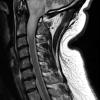

NEOPLASMS (GLIAL)

Astrocytoma, IDH-mutant, WHO Grade 2 (4)